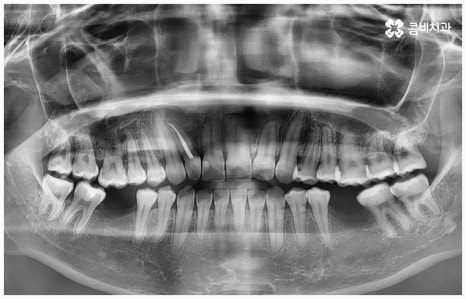

임플란트 종류 는 환자분들의 상황에 따라 달라지기 때문에 먼저 꼼꼼하게 정밀 검진을 받아보고 숙련된 의료진과 충분히 상담을 해 볼 필요가 있습니다. 환자분들의 치아 및 잇몸과 뼈의 상태, 전신 건강 등을 종합적으로 살펴보고 만약 필요하다면 선행 치료부터 받게 될 거예요. 선행 치료는 보통 임플란트 식립을 하게 된 치아 상실의 원인, 그리고 치아가 상실된지 얼마나 오랜 시간이 흘렀는지 여부에 따라 달라지는데 예를 들어 비교적 어린 나이에 큰 사고를 당해서 치아를 잃게 되었을 때 지체없이 바로 치과로 내원한 경우, 잇몸뼈가 건강하고 나이 등 회복력에 대한 기대치도 높은 편이며 다른 전신 질환, 상용약 등 잇몸에 지속적인 영향을 줄 만한 요소가 없다고 한다면 별다른 선행치료 없이 임플란트 종류 중 당일 심고 바로 임시 치아로 식사를 할 수 있는 원데이 임플란트를 통해 보다 빠르고 간편한 수복을 할 수 있어요.

보통은 인공 치근을 식립한 후에 얼마 동안 시간을 두어 골유착이 잘 일어나게 한 후에 지대주(연결 부위)를 연결하고 크라운 보철물을 제작, 장착해 주는데 여기서 개개인의 상황이 모두 다르기 때문에 회복 기간이 얼마나 걸릴지 정확하게 알 수는 없지만 대부분 3~6개월 정도라고 보면 될 거예요. 그동안은 불편한 상태로 사용을 할 수 밖에 없는데 만약 검진 및 발치, 식립, 임시 치아 제작 및 장착까지 모두 하루 만에 이루어진다면 임플란트 치료 기간을 줄일 수 있을 뿐 아니라 내원 횟수 및 통증과 불편감 또한 감소시킬 수 있을 것이기 때문에 시간적인 여유가 많지 않은 직장인분들, 학생들, 유학생분들이나 지방에 거주하시는 분들과 같은 경우에 임플란트 종류 중 원데이 임플란트 식립에 대해서 관심을 많이 보이고 있습니다. 그러나 말씀드린 것처럼 누구나 받을 수 있는 것은 아니기 때문에 먼저 잇몸뼈의 상태를 꼼꼼하게 체크하여 가능성 여부를 알아볼 필요가 있으니 검진 및 상담부터 진행해 보시길 권유드리고 있어요.

비용이나 시간적인 부담이 만만치 않기 때문에 임플란트를 보다 오랜 기간 동안 건강하게 사용하려면 어떻게 해야 하는지 궁금해 하시는 분들이 많이 있으실 거예요. 임플란트 식립 성공률 및 지속률에 가장 크게 영향을 주는 것은 환자분들의 잇몸뼈 건강 상태 및 술자의 숙련도라고 할 수 있는데요. 예를 들어 구강 질환을 원인으로 한 병증이 심각하거나 치아를 상실한지 오랜 시간이 지나 잇몸뼈의 흡수가 많이 일어났기 때문에 높이와 밀도 등이 식립을 진행하기에 충분하지 않다면 뼈이식을 선행하여 기반부터 튼튼하게 보충해 줄 필요가 있어요. 또한 노화로 인해 상악동이 내려왔다면 상악동 거상술을 통해 공간을 확보해 주어야 하는데 이렇게 고난도 수술의 경우 다양한 임상 경험을 통해 풍부한 노하우와 뛰어난 기술력을 가지고 있는 의료진과 함께 하는 것이 무엇보다 중요하다고 할 수 있습니다.